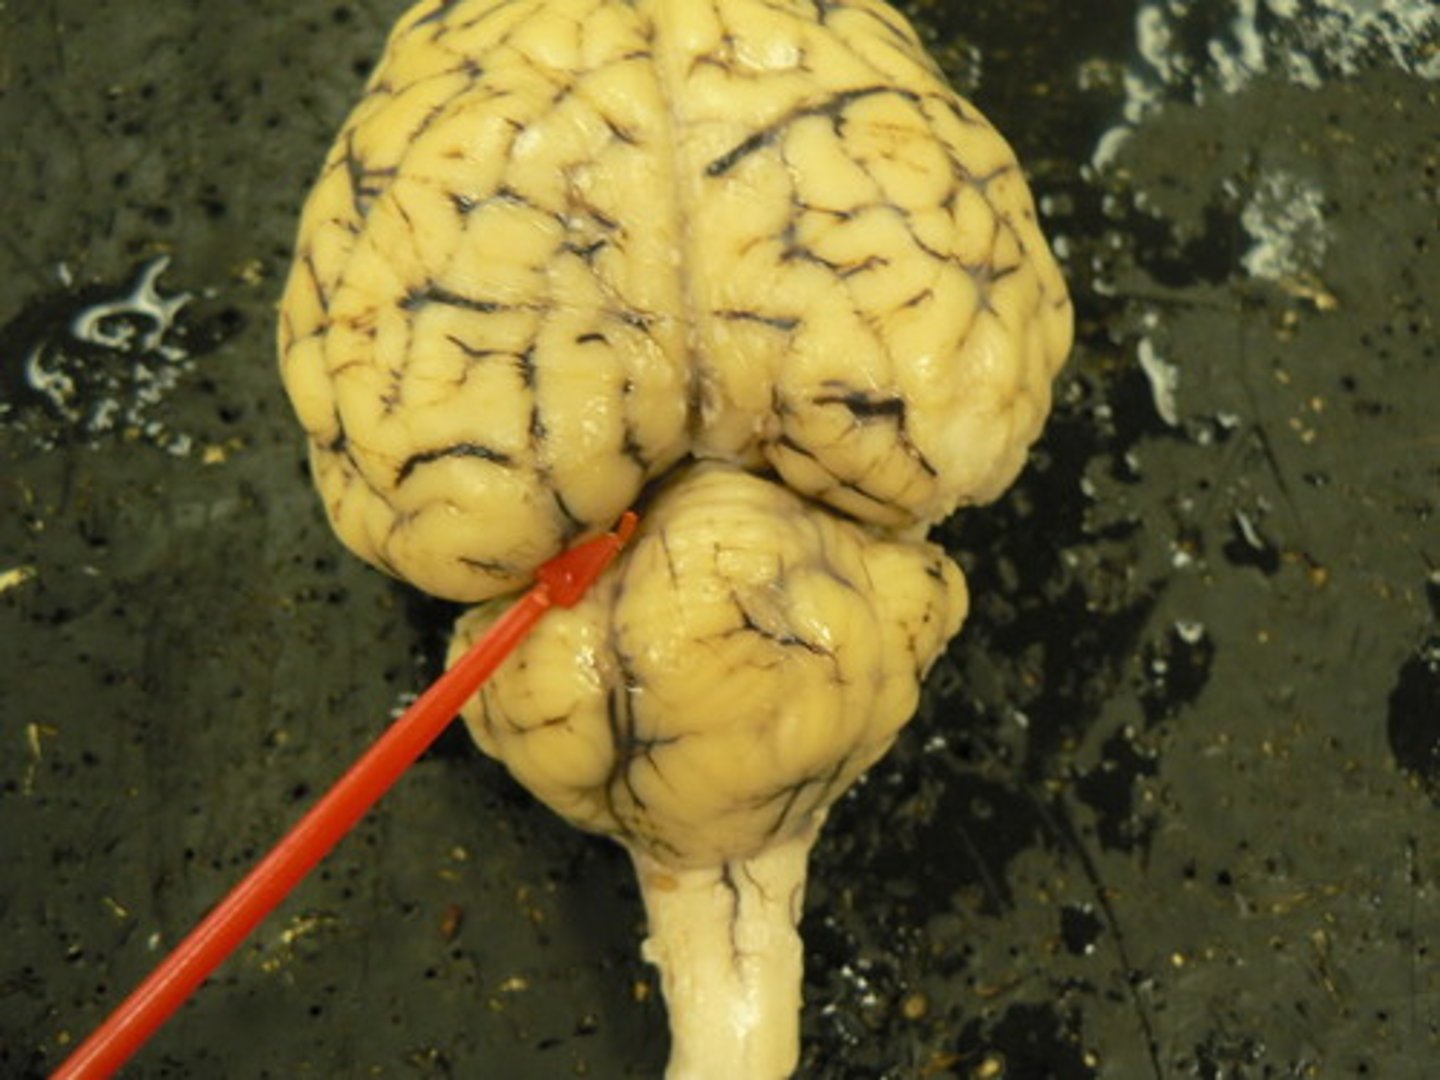

gyrus

folds in the brain (blue arrow)

fissure

deep depressions in brain folds

sulcus

shallow groove in brain